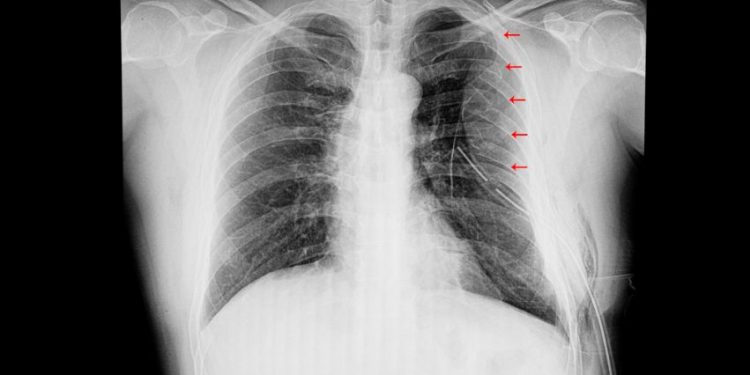

X-rays of the chest are the most common imaging technique used to diagnose pulmonary contusion. However, it takes an average of six hours for the characteristic white region to appear on a chest X-ray and sometimes, contusions are not visible until 48 hours after the injury.

In the early post-injury period, chest X-rays are not sensitive enough to detect lung contusion and further CT examination is required. Chest CT is 38-81% more sensitive than X-ray to diagnose pulmonary contusion.